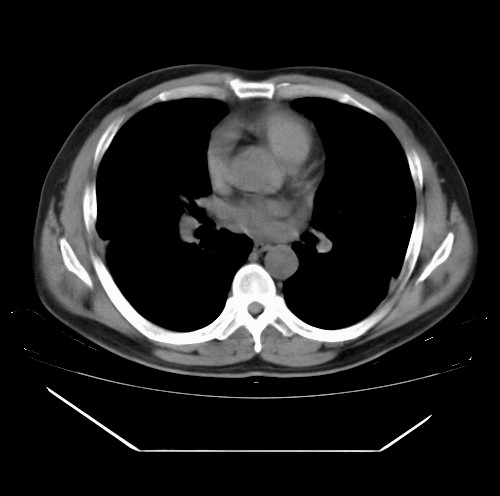

标题: CT22085:双肺多发结节

男,44岁,咳嗽,痰中带血2天。

除肺内及胸膜下可见多发大结节外,在肺小叶中心核、小叶间隔及支气管血管束上亦可见多方小结节,可以认为是随机分布。考虑转移可能性大。

仔细观察病灶形态,病灶边界部分清楚,结合临床症状,首先考虑转移,纵隔内多个肿大淋巴结影。

双肺血管纹理末端多发类圆形结节,边界光滑清晰 气管前腔静脉后淋巴结肿大

考虑转移瘤

沿血管分布,位于血管末端。转移瘤多见,血行性菌栓也可见到。

本例双肺多发类圆形高密度灶,边清,结合病史多考虑双肺多发转移改变,可以结合实验室检查。